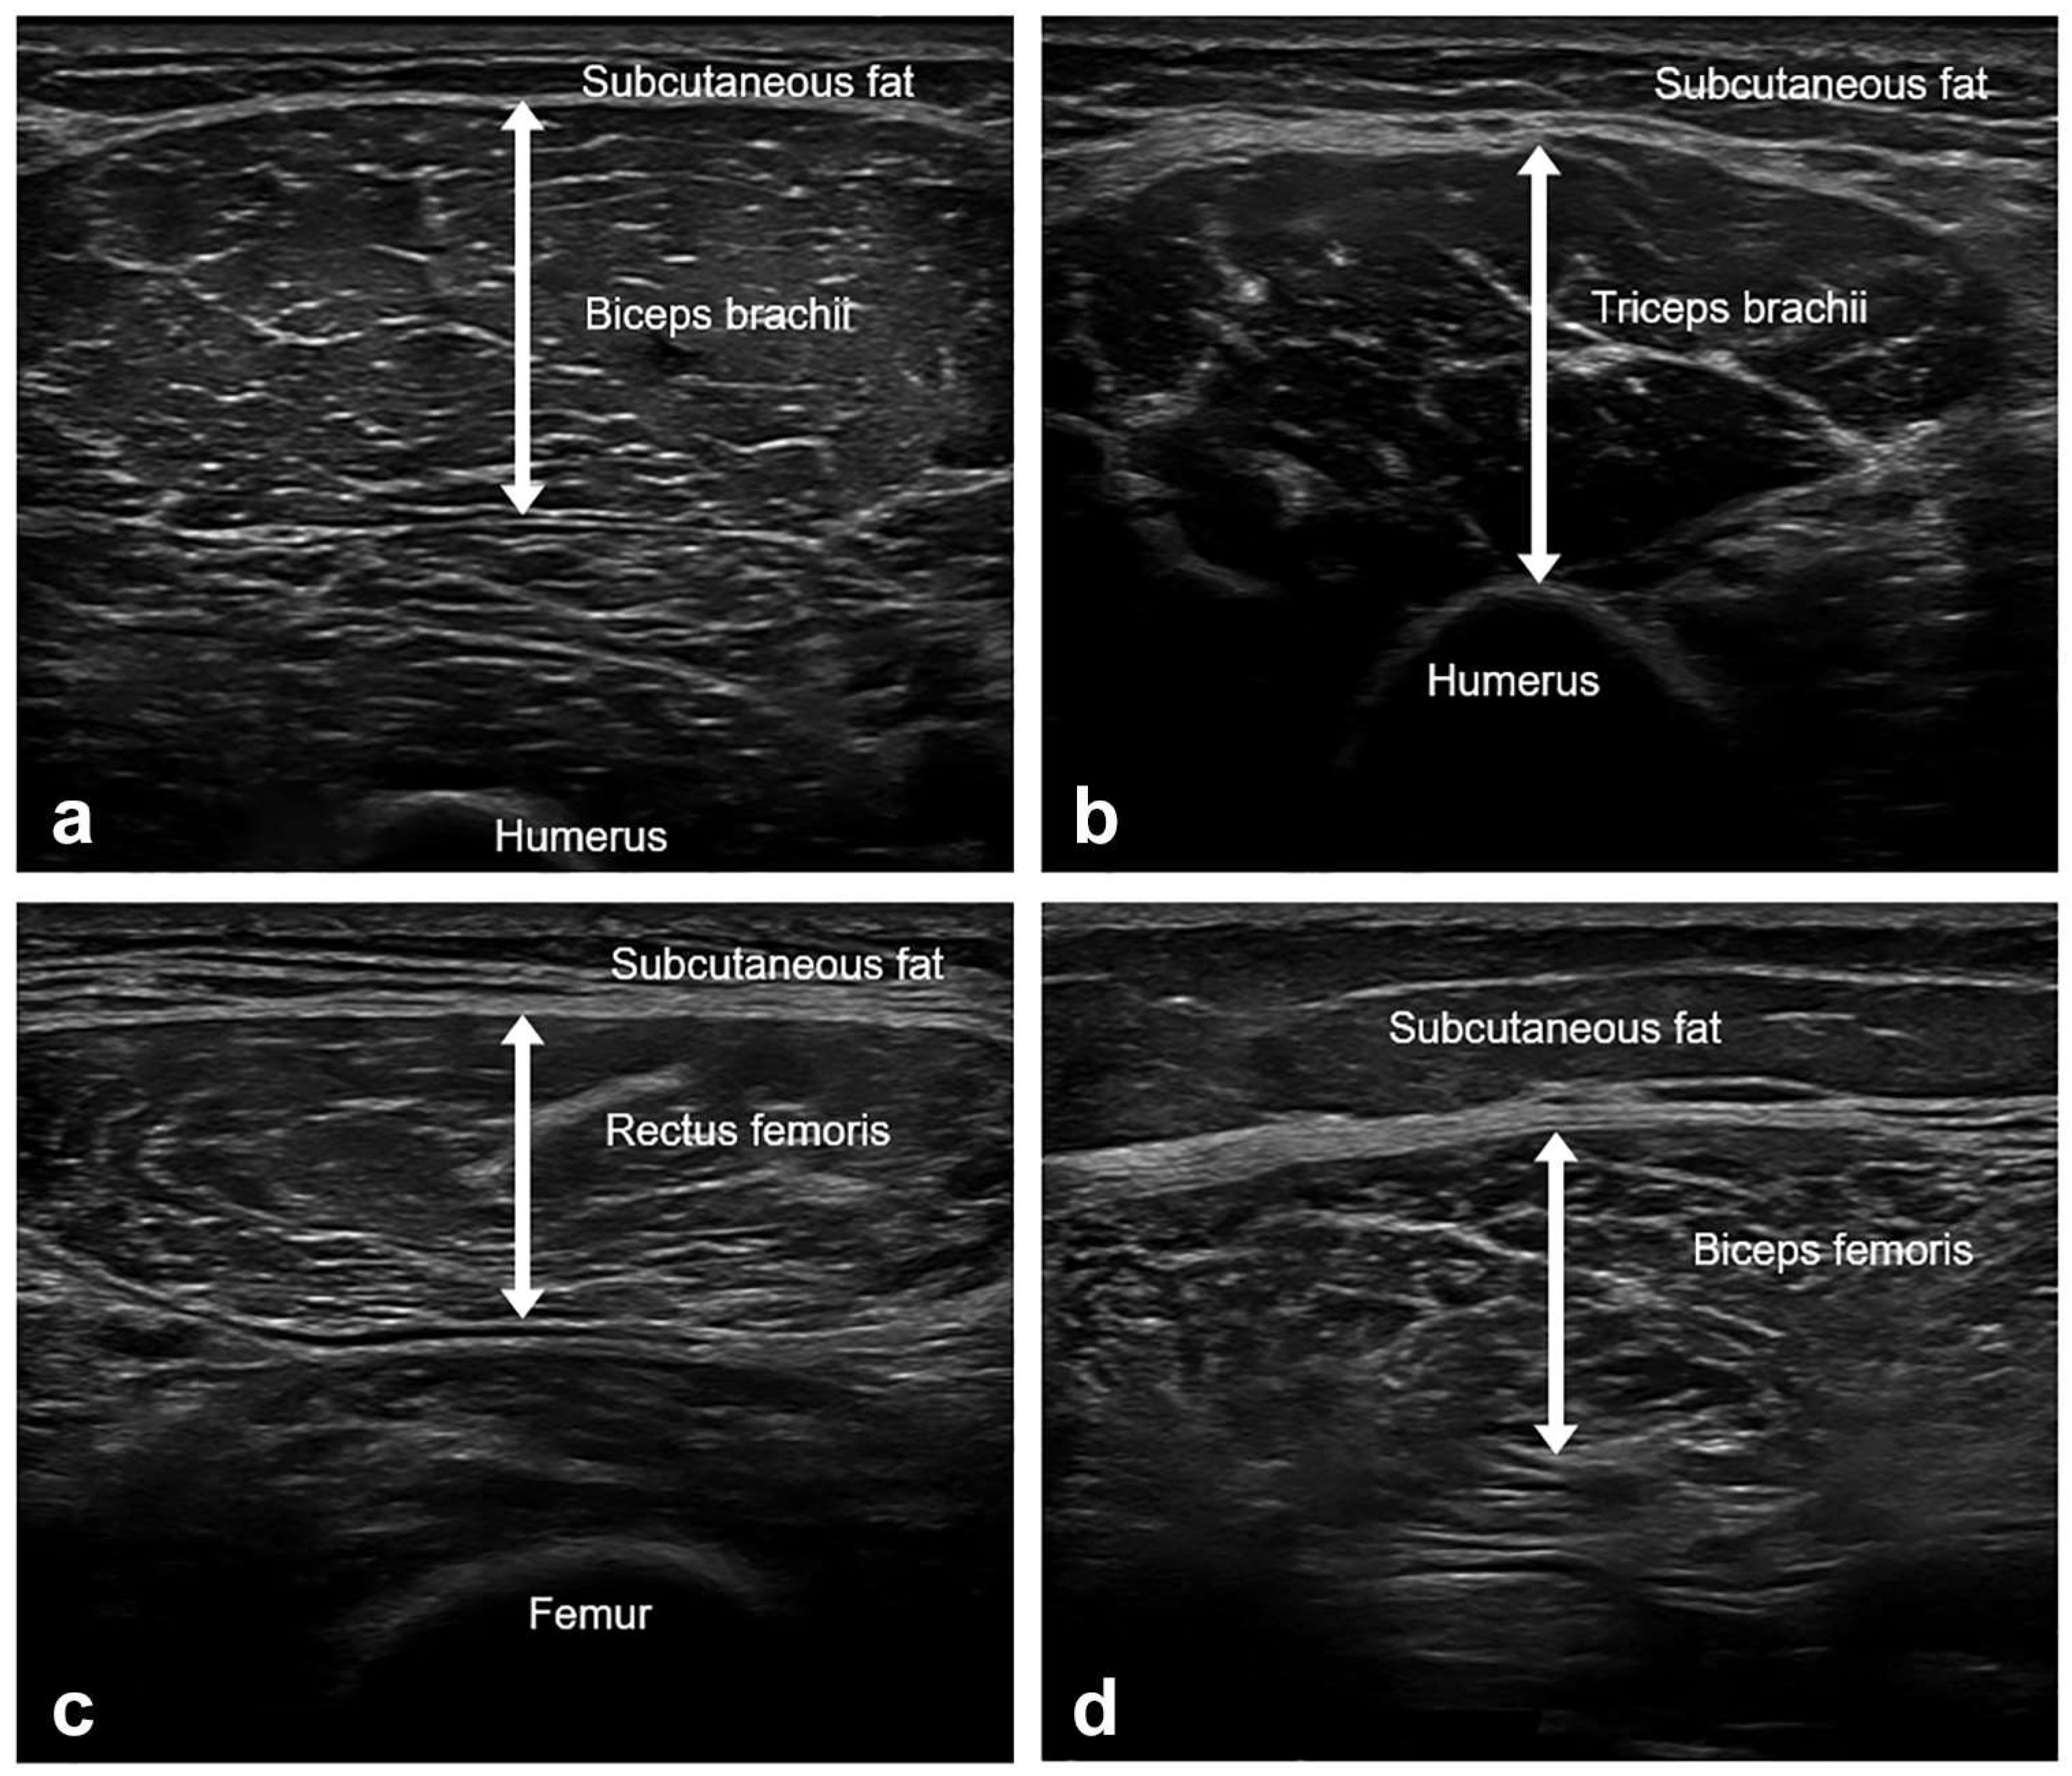

The thickness of four muscles (biceps brachii, triceps brachii, rectus femoris, and biceps femoris) was measured on the dominant side using B-mode US imaging (Aplio i700, Canon, Otawara, Japan) with an 18-Mz linear array transducer (Figure 1). The participants were examined with full relaxation, shoulder and hip in the neutral position, and elbows and knees in full extension. The biceps brachii (BB), triceps brachii (TB), and rectus femoris (RF) were examined in the supine position, while the biceps femoris (BF) was examined in the prone position. Care was taken to apply minimal pressure on the skin and to keep the probe as perpendicular to the skin as possible throughout the examination. The muscle thickness was assessed using the following anatomical landmarks (BB, between the medial acromion and the cubital fossa at 1/3 distance from the cubital fossa; lateral head of TB, at the midpoint between the posterior crista of the acromion and the olecranon at 2 finger widths lateral to the line; RF, at the midpoint between the anterior superior iliac spine and superior aspect of the patella; and the long head of BF, at the midpoint between the ischial tuberosity and the lateral epicondyle of the tibia). The muscle thickness was measured at the maximal muscle bulk with the probe positioned on the transverse plane of the muscles. Muscle thickness refers to the distance between the deep and superficial aponeuroses of a muscle.

Figure 1.

Representative images of muscle ultrasound and muscle thickness measurements. (a) Biceps brachii, between the medial acromion and the cubital fossa at 1/3 distance from the cubital fossa. (b) Triceps brachii, at the midpoint between the posterior crista of the acromion and the olecranon at 2 finger widths lateral to the line. (c) Rectus femoris, at the midpoint between the anterior superior iliac spine and the superior aspect of the patella. (d) Biceps femoris, at the midpoint between the ischial tuberosity and the lateral epicondyle of the tibia. Muscle thickness was defined as the distance between the deep and superficial aponeurosis of the muscle. The measurements were taken at their maximal muscle bulk.